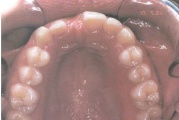

Normaalse jäävhammaskonna pilt küljelt ja eest vaadatuna.